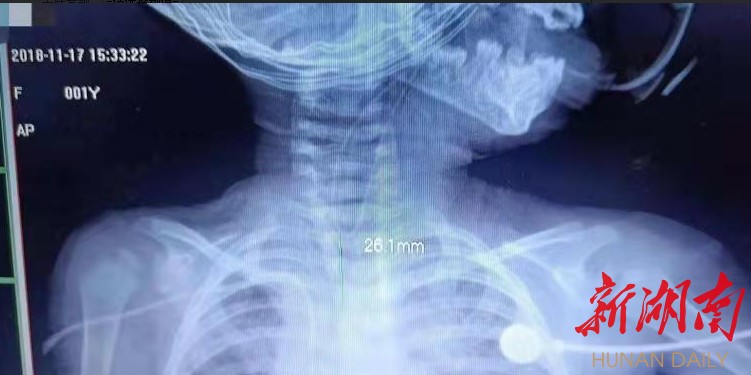

经过胸部X线和上消化道造影检查,也证实了儿童呼吸二区医师们的诊断。但是只是怀疑诊断为先天气管食管瘘,而胸部CT的确没有发现明显的瘘管,专家们分析认为患者有气管食管瘘,也可能只是肺炎。

经过医院多科的讨论,该院制定了详细并且有效地治疗方案,经过1周的抗感和营养支持后,患儿肺炎肺炎基本得到控制。本月17日,在全麻下给患儿做了“纤维支气管镜下经瘘管置入导丝术+一期食管气管瘘修补术”手术顺利,术后安返PICU,目前患儿病情平稳。